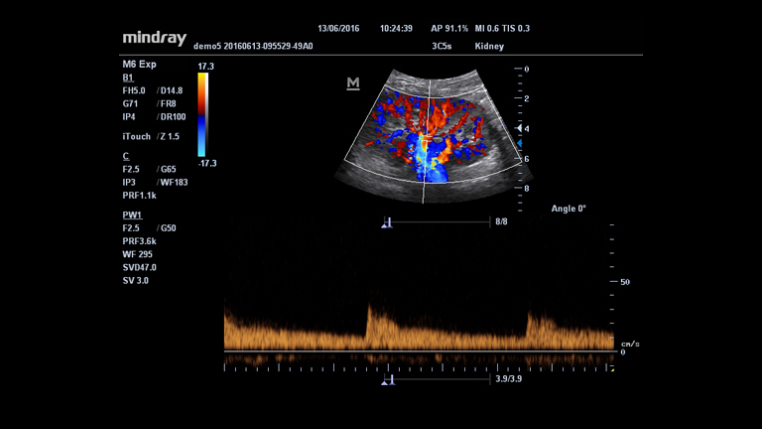

HR Flow?

?????? ???? ???? ????? ???? ??? ? ??? ?? ??? ?? ??? ???? ? ?? ???? ?????.